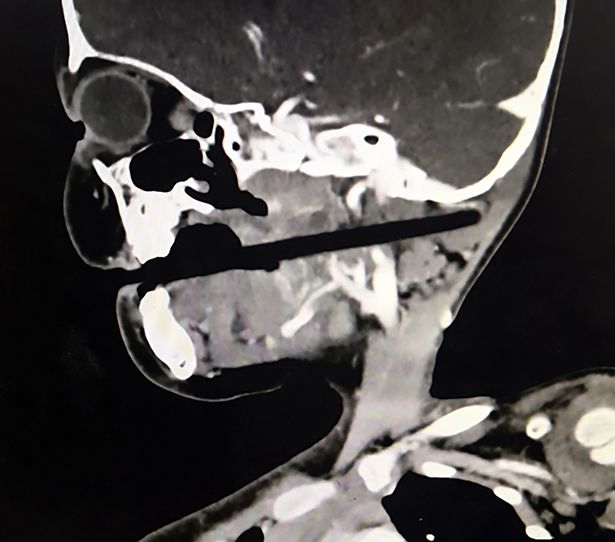

Ảnh chụp X-quang cho thấy, hộp sọ của cô đã bị thủng một lỗ. Có thể thấy, cây đũa đâm thẳng vào phần lưỡi gà và hướng lên trên ra sau gáy. Chiếc đũa đã bị mắc trong hộp sọ cô bé gần 8 giờ đồng hồ trước khi bác sĩ tiến hành phẫu thuật để loại bỏ dị vật ra khỏi cơ thể.

Ảnh X-quang cho thấy chiếc đũa bị mắc lại trong hộp sọ của cô bé